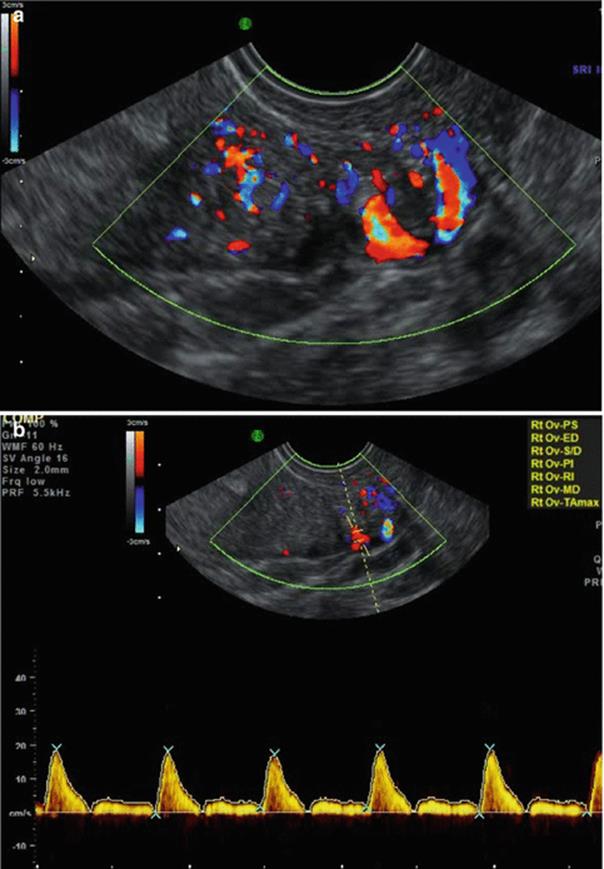

(a, b) Stromal blood flow

Stromal Blood Flow (Fig. 2.3a, b)

· Stromal Flow Index (FI) [6]

· <11 low responder

· 11–14 Normal responders

· >15 risk of OHSS

· Stromal Peak Systolic Velocity (PSV)

· Low stromal PSV in the early follicular phase predicts poor responders

· Increased stromal PSV with unchanged resistance predicts increased risk of OHSS